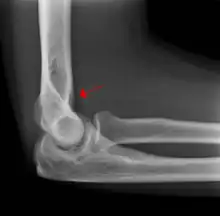

Fat pad sign

The fat pad sign, also known as the sail sign, is a potential finding on elbow radiography which suggests a fracture of one or more bones at the elbow. It is may indicate an occult fracture that is not directly visible. Its name derives from the fact that it has the shape of a spinnaker (sail).[1] It is caused by displacement of the fat pad around the elbow joint. Both anterior and posterior fat pad signs exist, and both can be found on the same X-ray.

The fat pad sign is invaluable in assessing for the presence of an intra-articular fracture of the elbow. An anterior fat pad is often normal. However a posterior fat pad seen on a lateral x-ray of the elbow is always abnormal. The patient will be unable to flex their elbow and requires orthopaedic input.[2]

The posterior fat pad is normally pressed in the olecranon fossa by the triceps tendon, and hence invisible on lateral radiograph of the elbow.[3] When there is a fracture of the distal humerus, or other pathology involving the elbow joint, inflammation develops around the synovial membrane forcing the fat pad out of its normal physiologic resting place. This is visible as the "posterior fat pad sign" and is often the only visible marker of a fracture, particularly in the pediatrics population.